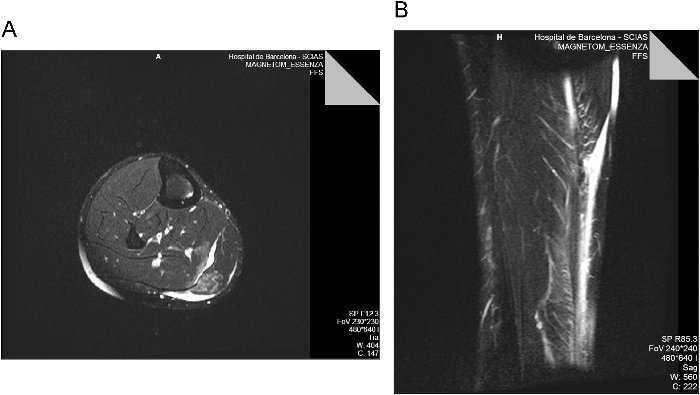

La segona RM es realitza als 4 dies de la lesió, i aquesta vegada centrada al terç distal de la cama, sobre tendó dAquil·les, i sobjectiva una ruptura parcial distal del tendó dAquil·les daproximadament 75% del gruix total del tendó (figura 2).

Figura 2. Imatges de ressonància magnètica: a) tall sagital stir, on observem una ruptura parcial extensa del tendó daquil·les, amb un gap ocupat per líquid i retracció de les fibres anteriors del tendó, i b) tall axial potenciat en T2 a nivell de lastràgal on observem aproximadament una 75% de desaparició del tendó dAquil·les amb preservació d eles fibres més posteriors.

Lecografia músculo-esquelètica dels primers tres dies sempre son indicatives duna lesió de tennis leg amb afectació principal del m. bessó intern. Com que existeix la sospita de lalteració del m. soli demanem la primera ressonància ja que per eco no es visible normalment11. La primera RM feta tenia una finestra de 25cm amb talls de 5–8mm centrada sobre la inserció distal del m. bessó i per tant en cap moment es visualitzava la inserció distal del tendó daquil·les. La segona RM feta amb el mateix aparell i equip de radiòlegs agafa una finestra de 25cm a nivell de 1/3 distal de la cama i es troba una imatge clara amb una ruptura parcial extensa del tendó dAquil·les. (veure figura 4).